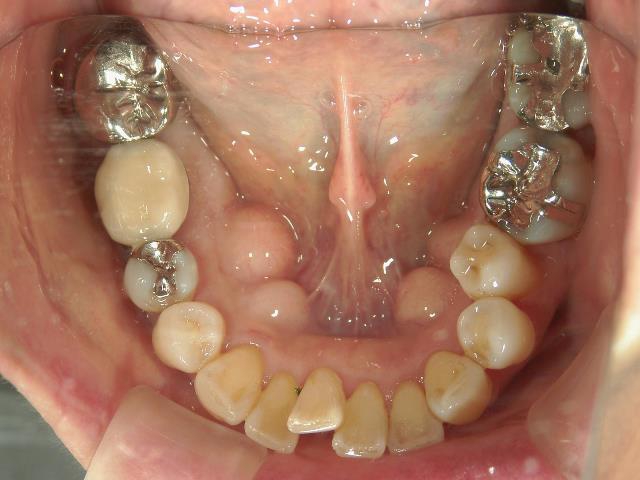

矯正歯科 治療前